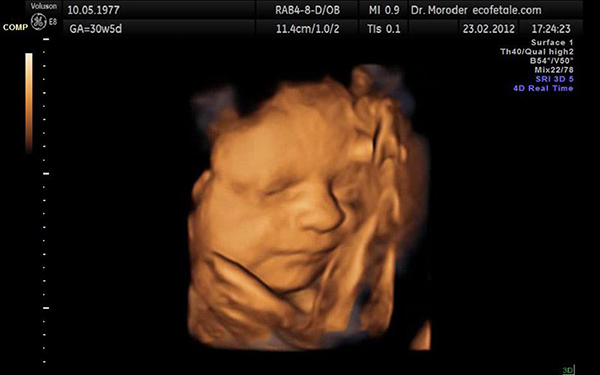

Thời điểm mà bạn nên thực hiện siêu âm 4D lần thứ 2 đó là vào khoảng tuần thứ 21 đến 24 của thai kỳ. Lúc này, bé sẽ được đo các chỉ số để biết em bé có đang phát triển bình thường hay không.

Khi siêu âm 4D lần 2, bác sĩ còn có thể xác định một số những dị tật như: hở hàm ếch, các bệnh lý liên quan đến nội tạng như tim, phổi, thận,…

Như đã nói thì tuần thứ 21 là tuần đánh dấu những chuyển biến rõ rệt của cơ thể bé. Lúc này, em bé gần như đã hình thành đầy đủ các cơ quan, bộ phận và mẹ có thể nhìn thấy thai nhi một cách khá rõ nét. Vì thế, bạn không nên lăn tăn nữa mà hãy tìm gặp bác sĩ để nhận được tư vấn xem thai 21 tuần siêu âm 4D hay không cho trường hợp của mình nhé.

Sau đây sẽ là một số chỉ số thai 21 tuần siêu âm 4D mà bạn sẽ thấy khi đi siêu âm:

– Chỉ số BPD: đây là đường kính lưỡng đỉnh. Chỉ số này nếu nằm trong khoảng từ 44 đến 56 thì là tốt

– Chỉ số FL: đây là chỉ số đo độ dài xương đùi. Thai 21 tuần siêu âm 4D sẽ được coi là phát triển bình thường nếu chỉ số FL nằm trong khoảng từ 32-38.

– Chỉ số AC: chỉ số này sẽ cho biết chu vi vòng bụng. Lúc này, vòng bụng của bé sẽ nằm trong khoảng từ 147 đến 187.

– Chỉ số EFW: khi thai 21 tuần siêu âm 4D, bạn sẽ thấy cân nặng của bé có mức trung bình nằm trong khoảng từ 331-467.

– Chỉ số HC: là chỉ số biểu thị chu vi vòng đầu. Ở tuần 21, chu vi vòng đầu của bé sẽ nằm trong khoảng từ 170-200.